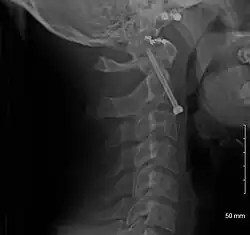

Fractures

Repair of a dens fracture

A fracture of both pedicles of the axis is termed a Hangman's fracture.

Fractures of the dens are classified into three categories according to the Anderson Alonso system:

• Type I fracture - Extends through the tip of the dens. This type is usually stable.

• Type II fracture - Extends through the base of the dens. It is the most commonly encountered fracture for this region of the axis. This type is unstable and has a high rate of non-union.

• Type III fracture - Extends through the vertebral body of the axis. This type can be stable or unstable and may require surgery.[1]